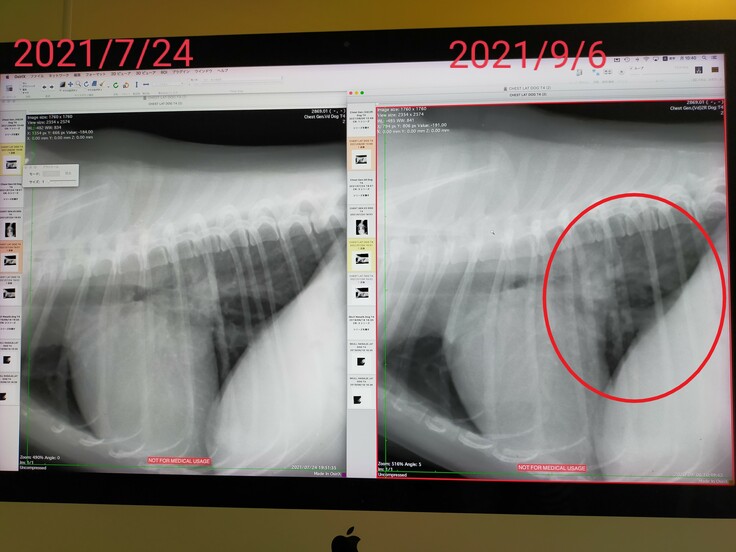

2021/9/6、歯の定期検診に行った際に咳が酷かったので、レントゲンを撮った所、肺水腫を起こしていると言われ、利尿剤といつも貰っているのとは違うピモベハートという心臓のお薬が出ました。

●右側の赤丸で囲った所が左の写真に比べて白く濁っています。

ここは肺なので左の写真のように黒く映っていないといけないのですが、肺水腫をおこして白く濁っています(写真のアップロードの許可はいただいています)